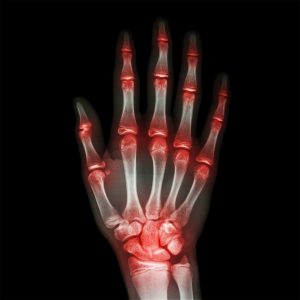

Hand and wrist scans

Tendon inflammation and rupture can be visualised, also lumps and bumps, even glass or thorn (foreign bodies) can be seen within the finger.

Hand and wrist injuries are also common and can affect ligaments, joint surfaces, tendons and muscles.

Hand/Wrist scan £135